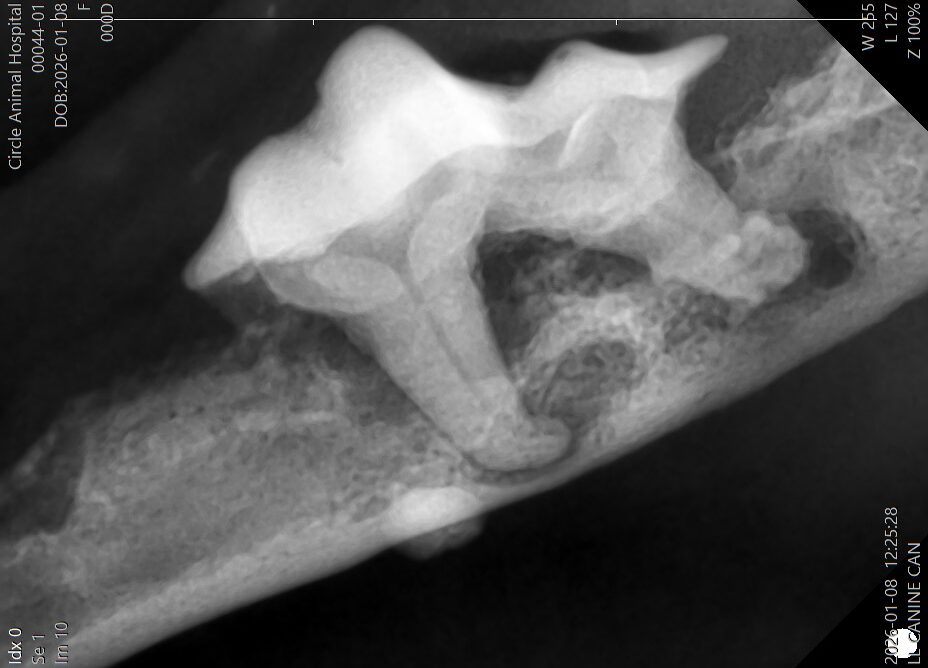

その後に、歯科レントゲンを撮影し、肉眼では見えない歯の根っこの部分を評価します。

レントゲンでは、

・歯を支える骨(歯槽骨)が大きく溶けている

・歯根の周囲に炎症が広がっている

状態が確認されました。

見た目以上に、歯周病は深く進行していました。

特に右下顎の歯根部では下顎骨がかなり溶けてしまっており、骨折する可能性がある状態でした。